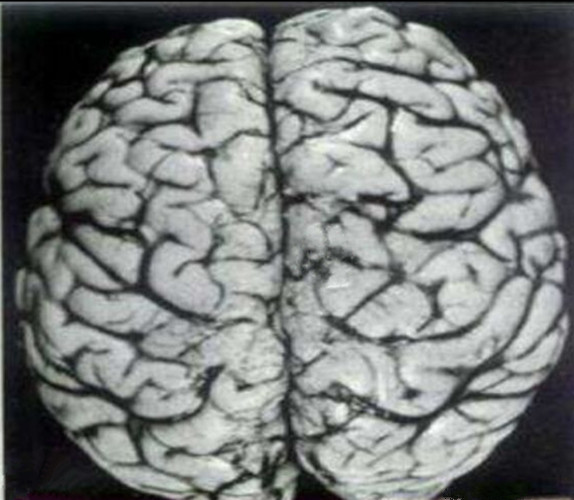

腦膜炎早期的

腦膜炎早期